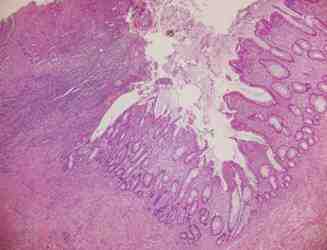

Figura 2. Anatomía Patológica (AP): adenocarcinoma invasivo de colon

Figura 4. AP: regresión 4 de Dworak, ulceración y fibrosis